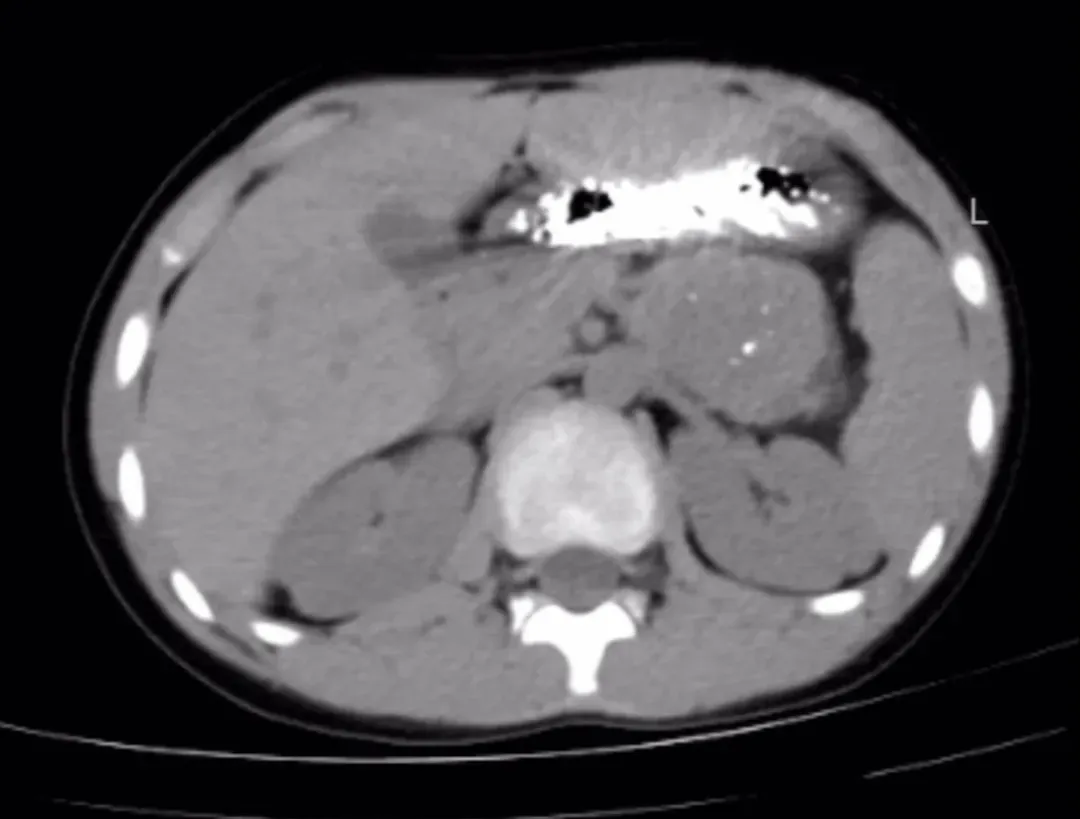

近日,一场由“甜蜜冬枣”引发的健康危机在延安市中医医院(北京大学第三医院延安分院)儿科上演,一名10岁患儿在食用大量冬枣后,突发剧烈腹痛、呕吐伴腹胀,腹部CT提示胃内大量内容物堆积,伴发小肠梗阻征象,情况危急。儿科潘维伟主任与屈晖副主任根据明确的饮食史与影像依据,快速诊断为极为罕见的“植物性胃结石并发肠梗阻”。

入院影像检查